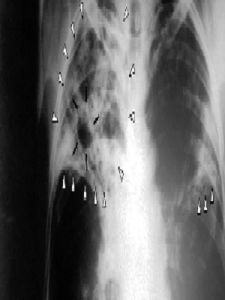

預防肺結核(1)X線檢查肺部有滲出性病變、乾酪性病變並周邊滲出性病變、空洞、增殖性病變(血播型肺結核病),從未抗結核治療過的病人;

(2)X線檢查肺部有滲出性病變、乾酪性病變並周邊滲出性病變、空洞、增殖性病變(血播型肺結核病),正在進行規律抗結核治療未完成規定療程的病人;

(5)原菌陰病人抗結核治療>3個月,或初治菌陽抗結核治療>5個月、復治菌陽抗結核治療>6個月,中斷治療>2個月,本次痰結核菌檢查陰性,但X線檢查肺部結核病變較上一次胸片的病灶明顯增多或/和有新的空洞形,或結核中毒症狀明顯,血沉增快者;如僅有本次胸片,至少觀察3個月後,若新發現活動性病變、病變較前增多、新出現空洞、痰菌轉為陽性,均視為活動性肺結核。